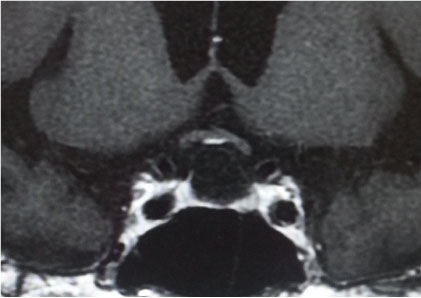

<画像所見>

・頭部MRI T1強調画像(1ヶ月前)